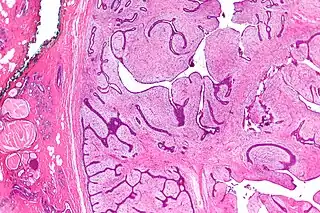

![]() Micrografía de un cistosarcoma filoides (a la derecha de la imagen). | ||

El tumor filoides es el neoplasia no-epitelial más frecuente en las mamas, pero representa solo un 1% de todos los tumores de la mama. Es un tumor de crecimiento rápido, bajo el microscopio puede ser un tumor de pocos centímetros o bien puede presentar lesiones masivas de hasta 30 cm.[1] El aspecto es carnoso, blanco o grisáceo y firme, lobulado con hendiduras quísticas y áreas de necrosis y hemorragia. Tiene cierto parecido histológico al fibroadenoma, pero luce con mayor celularidad, el epitelio es benigno con un estroma que rodea al epitelio de características atípicas e hipercelular.[2]